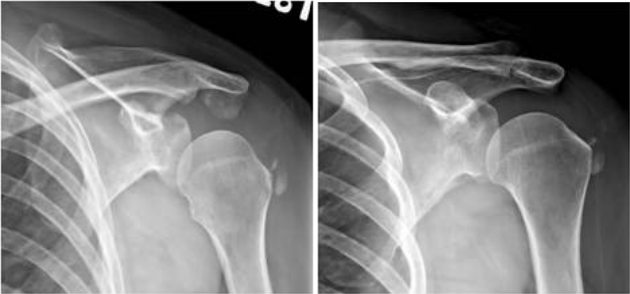

72.59歲女性一個月前跌倒後出現左肩疼痛的症狀,影響睡眠,肩關節X光檢查如附圖,最可能的診斷為何?

(A)avulsion fracture of greater tuberosity(B)calcified tendinosis(C)bone metastasis (D)primary osteoblastic bone tumor